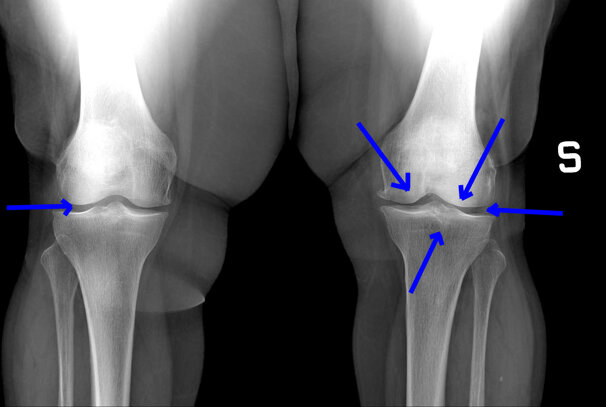

L'artrosi del ginocchio, come tutti immaginiamo, è una malattia molto frequente nella nostra società e, in considerazione della crescente aspettativa di vita, in continuo aumento, con una frequenza che varia dal 27% al 44% (popolazione sopra gli ottant’anni).

Qualora, per diverse ragioni, non si scelga di eseguire l’intervento ortopedico di protesi, o anche nell’attesa di effettuarlo, una valida terapia è ormaida anni rappresentata dalla viscosupplementazione a base di acido ialuronico, mediante infiltrazioni intra-articolari.

L’utilizzo del solo acido ialuronico in sé, non ha effetti antiinfiammatori significativi e può comunque solo ridurre parzialmente il danno cartilagineo.

Per questo motivo l’associazione con ossigeno-ozonoterapia, mediante la stessa via intra-articolare, determinando un effetto anti-infiammatorio e anti-dolorifico, migliora la sintomatologia globale dell’artrosi al ginocchio.

Tale vantaggio è stato anche dimostrato da un recentissimo lavoro scientifico, che ha comparato i diversi gruppi di pazienti e dalla quale è emerso che gli effetti più positivi sono scaturiti dal gruppo di soggetti trattati associando l’ozono e l’acido ialuronico.